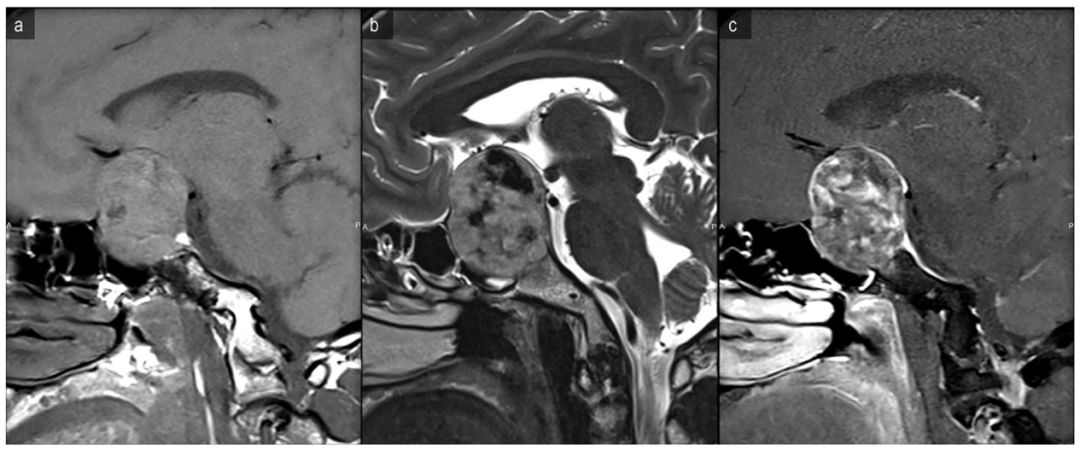

此外,该疾病还需与其他鞍区富血管类疾病鉴别,如鞍区颗粒细胞肿瘤,此类肿瘤起源于垂体细胞,质地偏硬,血管丰富,手术切除困难;另外,还需与垂体腺瘤伴卒中鉴别,镜下除可见出血坏死组织外,还可见遭破坏的排列混乱的肿瘤上皮细胞;而海绵状血管瘤镜下可见大小不一的血管组织,中间夹杂许多红细胞。Al-Sharydah等报道一例鞍区海绵状血管瘤,术前MRI显示病灶为混合信号,增强不均匀(图7);术后病理提示:病灶内可见大量直径大小不一的血管,间质内可见大量红细胞及碎片,高倍镜下显示血管壁菲薄且未见任何胶质样细胞(图8)[8]。针对本病例,其术前MRI显示病灶内信号不均匀,增强扫描病灶边缘局部轻度强化,与该报道病例术前影像有所不同,我们在术前判断可能是颅咽管瘤或巨大垂体腺瘤;但术中,我们也发现病灶中大量黄色泥沙样坏死组织;病灶切除后,周围结构,诸如鞍隔、海绵窦内侧壁等解剖结构显示清楚,故与传统的颅咽管瘤或垂体瘤不一样;术后经病理检测,提示内含大量纤维组织,伴坏死细胞及丰富的陈旧性血肿,尽管未见明确的血管样结构,但亦未见明确的肿瘤上皮细胞,结合患者起病缓、病程长等特点,综合术中镜下及病理所见,我们倾向诊断为鞍内海绵状血管瘤,实属罕见。

图7. Al-Sharydah报道的鞍区海绵状血管瘤病例术前MRI